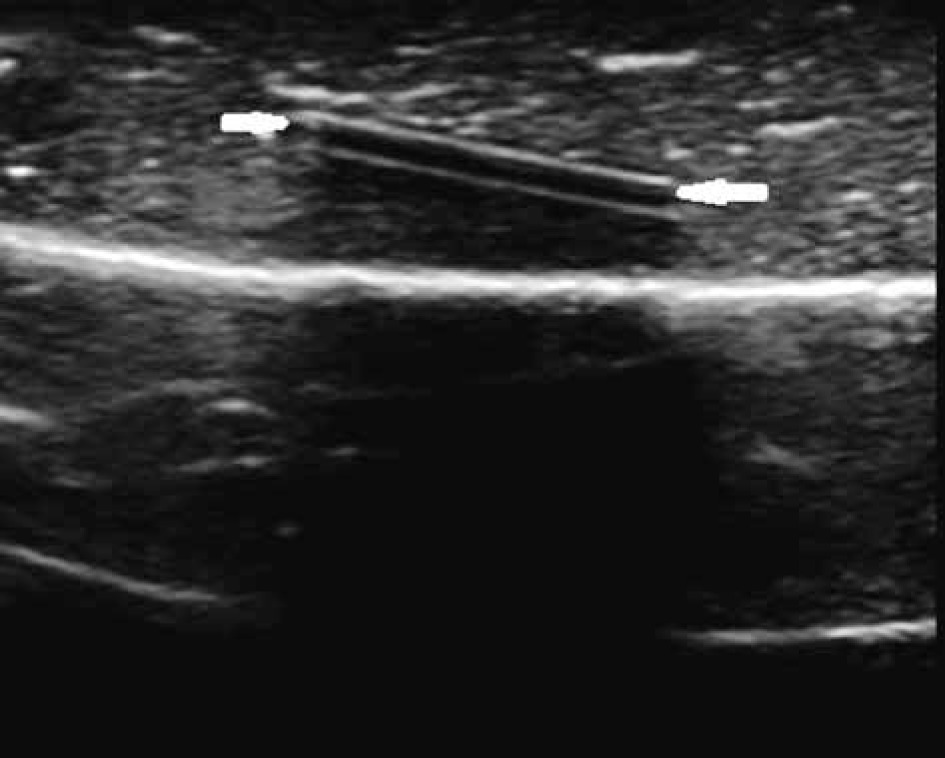

Figure 2

A plastic phantom in pieces of chicken fillet on ultrasonography, a hypoechoic line (white arrows) can be seen between the 2 hyperechoic linear lines

All the FBs examined in our study were hyperechoic (Figure 1). A hypoechoic line between the 2 hyperechoic linear lines was observed in the plastic FBs (Figure 2). We thought that this was due to the layered structure of plastic bodies formed during the production processes. Posterior strengthening was determined in FBs, which was more prominent in porcelain, walnut shell, peanut shell, and pellet.